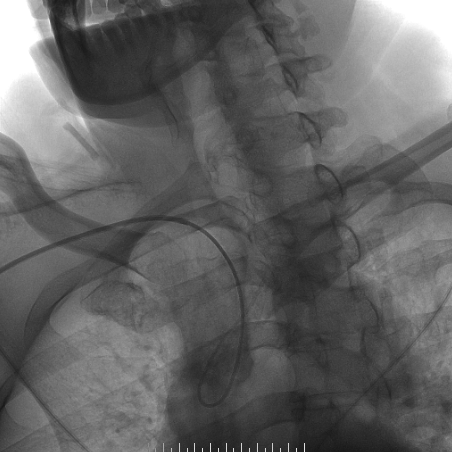

手术过程

-- 右侧桡动脉穿刺置入7F 泰尔茂薄壁鞘,波科7F0.081导引导管同轴5F 125cm SimmonsII导管在0.035导丝引导下引至左侧颈总动脉。

-- 路途引导下,FilterWire EZ保护伞顺利通过狭窄段至左侧颈内动脉岩骨水平段,顺利释放保护伞